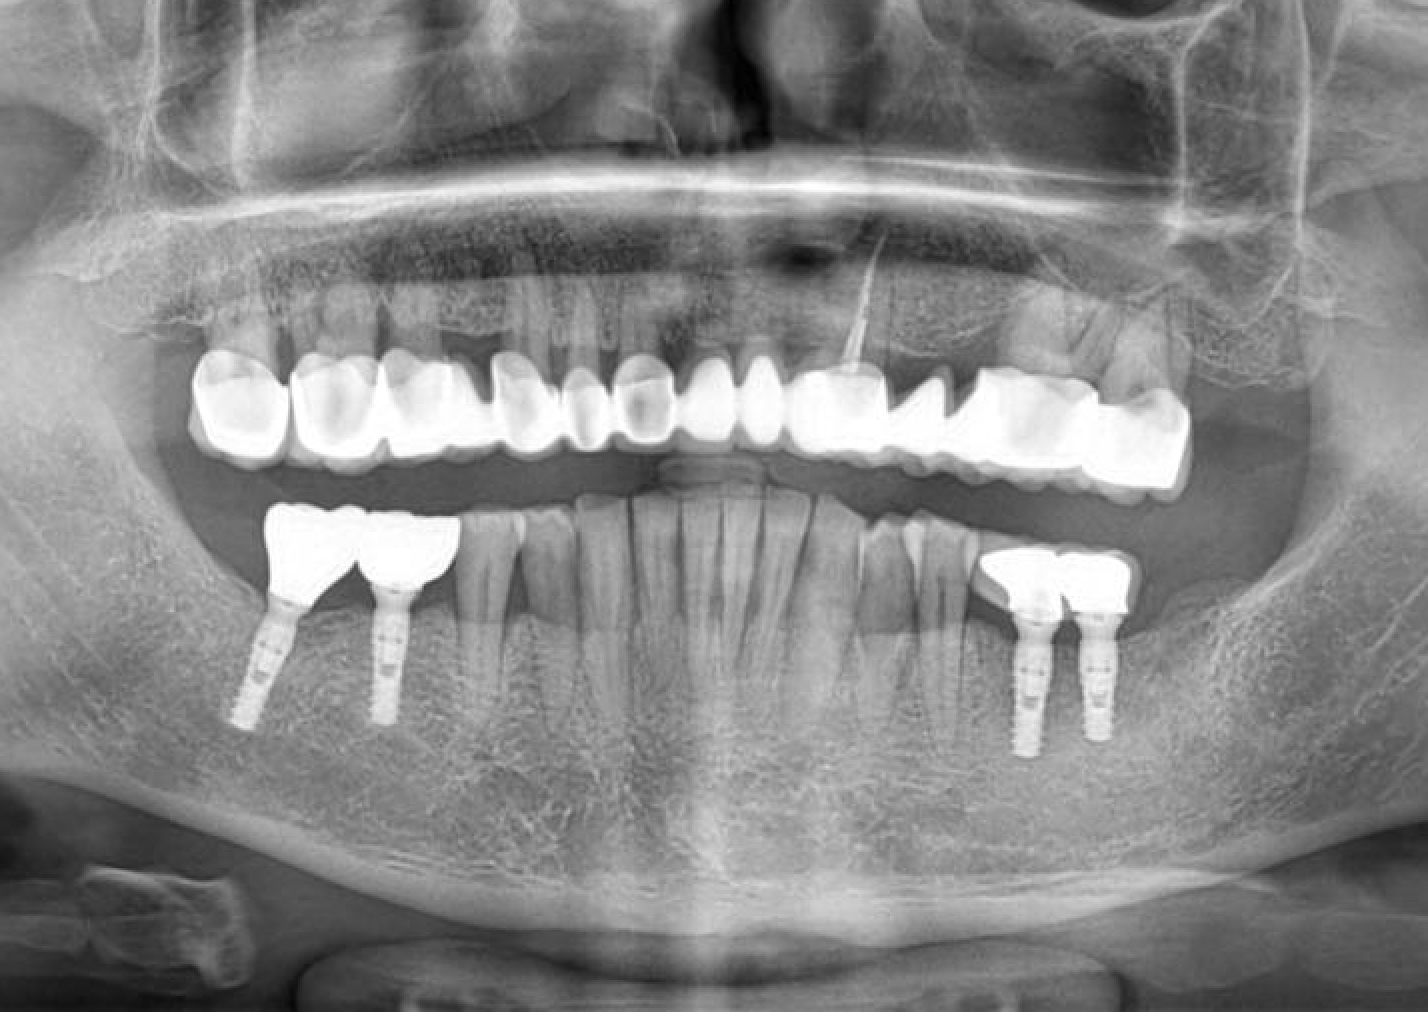

The effects of diabetes, smoking, and alcohol consumption on implant treatment are increasingly being investigated. This case presentation discusses successful implant treatment with Naxis implants in a male patient with high diabetes and heavy smoking-alcohol use. Additionally, X-ray images taken five years after the initial implant surgery are provided to…